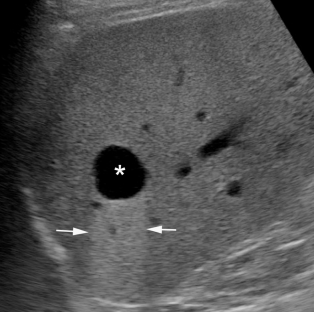

A vizsgáló orvos két fajta eltérést keres, az egyik a szerkezet általános, vagy nagyobb területet érintő elváltozása. Ezek az úgynevezett diffúz szerkezeti eltérések. (3. kép) A másik a körülírtabb eltérések, amelyeket fokálisként is szoktunk hívni (4. és 5. kép).

Diffúz szerkezeti eltérés például a zsírosodás vagy a májcirrózis, fokális szerkezeti eltérés lehet például egy haemangioma, ciszta, vagy daganat.

4. és 5. kép:

Példák körülírt elváltozásokra a májban.

4. képen egy cystát míg az 5. képen egy haemangiomát láthatunk. Ezek a leggyakoribb körülírt eltérések a májban.